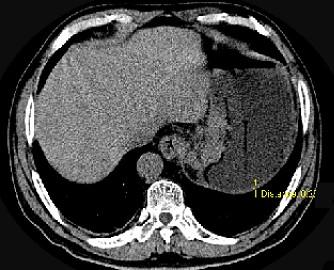

问题 男,75岁,吞咽有梗阻感,消瘦、乏力、中上腹痛,影像检查如图,最可能的诊断是 ( )

选项 A.食管癌 B.胃窦癌 C.贲门癌 D.慢性胃炎 E.胃淋巴瘤

答案 C